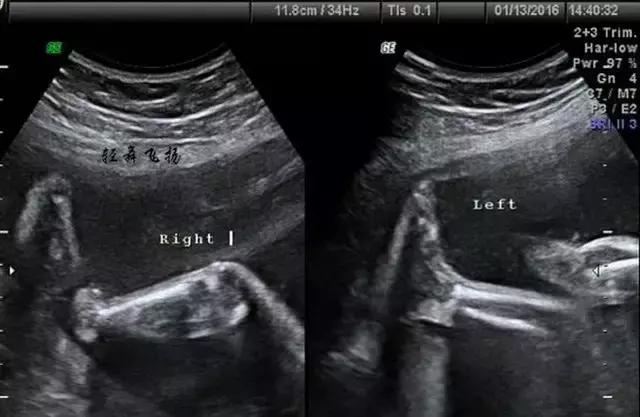

b.四肢